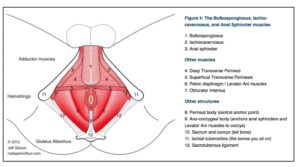

SUELO PÉLVICO

En el estrecho medio de la pelvis se insertan los músculos profundos del suelo pélvico. Por su disposición transversal y opuesta al diafragma torácico, también se lo denomina diafragma pélvico.